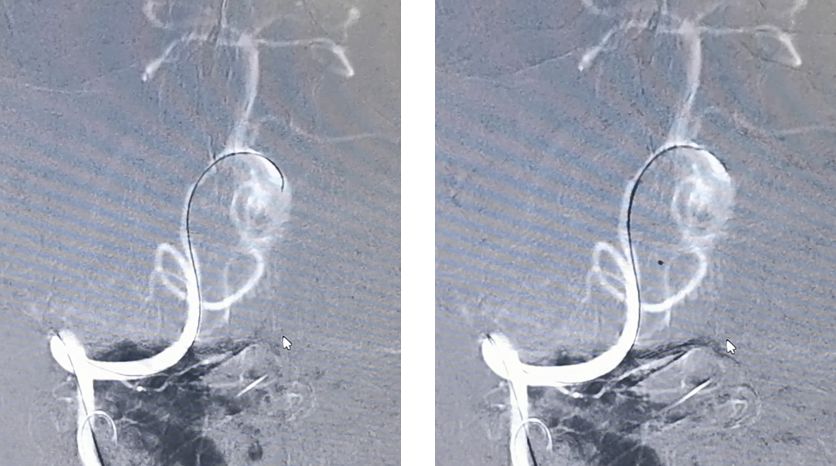

然后将Marksman微导管通过左侧椎动脉顺利进入左侧大脑后动脉

PED支架沿Marksman进入准备释放

释放PED。由于瘤颈很宽,所以PED需要足够长,动脉瘤远端和近端才能具有足够的锚定力量,防止支架坠入瘤腔内。所以,我们选择了3.25*35mm的支架。支架上端定位在基底动脉中段

PED释放完毕,位置及贴壁良好,左椎-基底动脉血运通畅,未填弹簧圈,即可见到瘤腔内造影剂的滞留,说明支架贴壁良好,起到了良好的重建作用